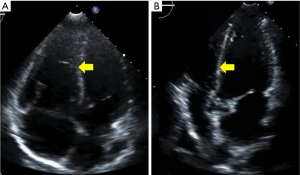

The PERT recommended further work up. Lower extremity venous ultrasound demonstrated evidence of a right popliteal deep venous thrombosis. Suspicion for intracardiac shunt as the source of the axillary arterial embolus prompted an evaluation with transthoracic echocardiogram with agitated saline “bubble study.” The echo revealed a mobile interatrial septum and early passage of “bubbles” from the right to the left atrium consistent with interatrial shunt likely patent foramen ovale (PFO) (Figure 6).